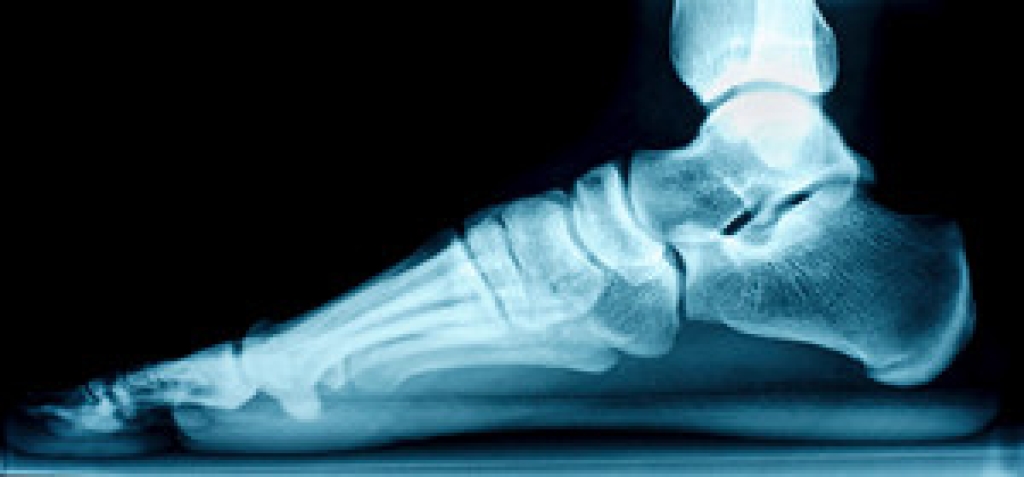

Choosing the right running shoe is essential to many runners. This can help them to achieve their running goals, which can range from training for a marathon to weekend jogging. One of the most important factors in choosing running shoes is choosing the right size. it is important to allow space approximately the size of a thumb at the top of the shoe. This can prevent the toes from moving forward while running downward. Additionally, it is beneficial for the upper part of the shoe to fit snugly against the foot, and this can prevent the foot from sliding. Knowing the type of running that will be done is crucial in buying the right type of shoes. Additionally, it is essential to know how many miles will be run, and if the surfaces are uneven trails or smooth ground. A podiatrist can help you to decide which type of running shoe is best for you, and it is suggested that you contact this type of doctor who can help you make the right choice.

Improper shoe sizing can cause a myriad of problems for your feet. Shoes that don’t fit you properly can lead to muscular imbalances in your body, which can result in foot, knee, and hip injuries.